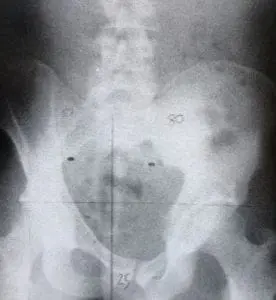

Cobbvinkel

Diagnos sätts efter röntgenundersökning där man kan se och mäta kurvaturerna och cobbvinkel. Cobbvinkel är sättet man mäter och klassificerar skolios. Över 10% behövs för diagnos.